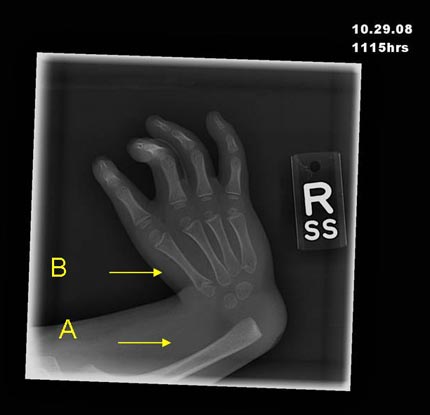

Radiograph of the right hand demonstrates complete absence of the radius (A) and first ray (B), including the thumb.